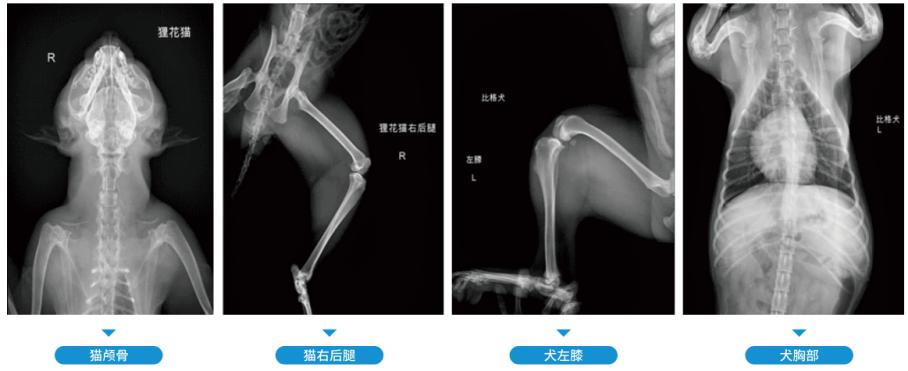

• 数字化X线摄影

数字化X线摄影

显示骨结构、关节软骨及软组织观察肠管积气、气腹和结石等病变胸部、心肺血管摄影